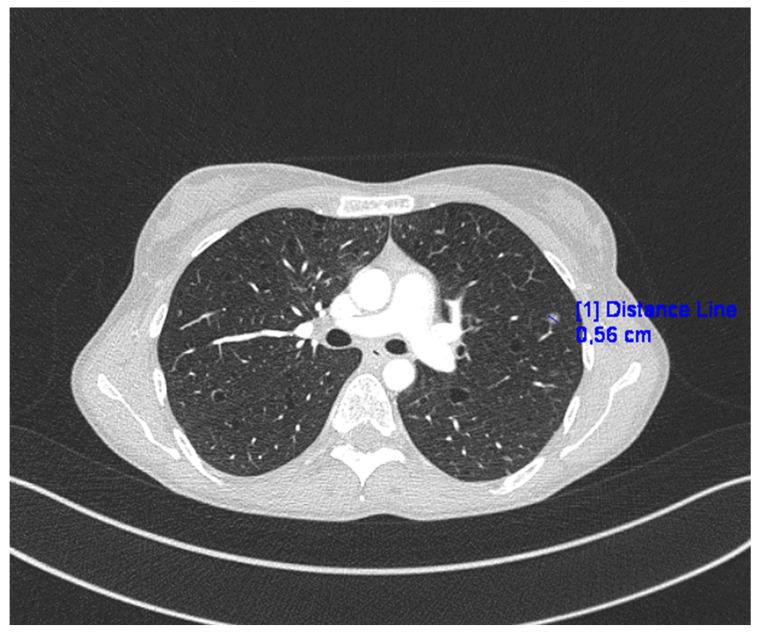

Lymphangioleiomyomatosis (LAM) is characterized by lung cysts that cause lung deterioration, changes in the lymphatic system, and tumors in the kidneys. It mainly affects women of reproductive age and is a progressive disease. LAM can occur as an isolated disease or coexist with tuberous sclerosis (TSC). The source of LAM cells is unknown. Patients with confirmed LAM should be treated with an mTOR inhibitor, sirolimus, or everolimus. We present a case of LAM with TSC in a patient whose symptoms, including those in the lymph nodes and chyaloperitoneum, mainly concern the abdominal cavity.

淋巴管平滑肌瘤病(LAM)的特征是肺囊肿会导致肺功能恶化、淋巴系统改变以及肾肿瘤。它主要影响育龄女性,是一种进行性疾病。LAM可作为一种孤立性疾病出现,或与结节性硬化症(TSC)共存。LAM细胞的来源尚不清楚。确诊为LAM的患者应使用mTOR抑制剂、西罗莫司或依维莫司进行治疗。我们报告一例合并TSC的LAM病例,该患者的症状,包括淋巴结和乳糜腹的症状,主要累及腹腔。